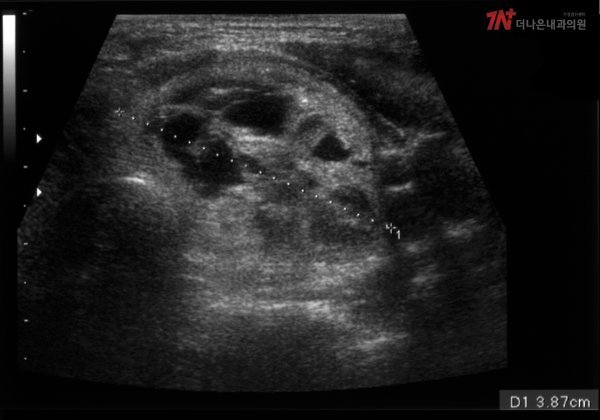

초음파 검사는 장기의 위치에 초음파 기구를 밀착시켜 내부를 살펴보는 내과 검사로 질환 조기 발견 및 치료를 목적으로 한다. 다양한 신체 부위의 구조와 형태는 물론 병변까지 실시간으로 확인할 수 있으며 통증의 원인을 찾거나 종양을 조기에 진단할 수 있다.

해당 검사는 방사선 노출의 부담이 없어 노인이나 임산부도 안전하게 받을 수 있으며, 특히 갑상선의 경우 초음파검사를 통해 CT나 MRI에는 잘 보이지 않는 갑상선 결절을 자세하게 확인할 수 있다는 장점이 있다.